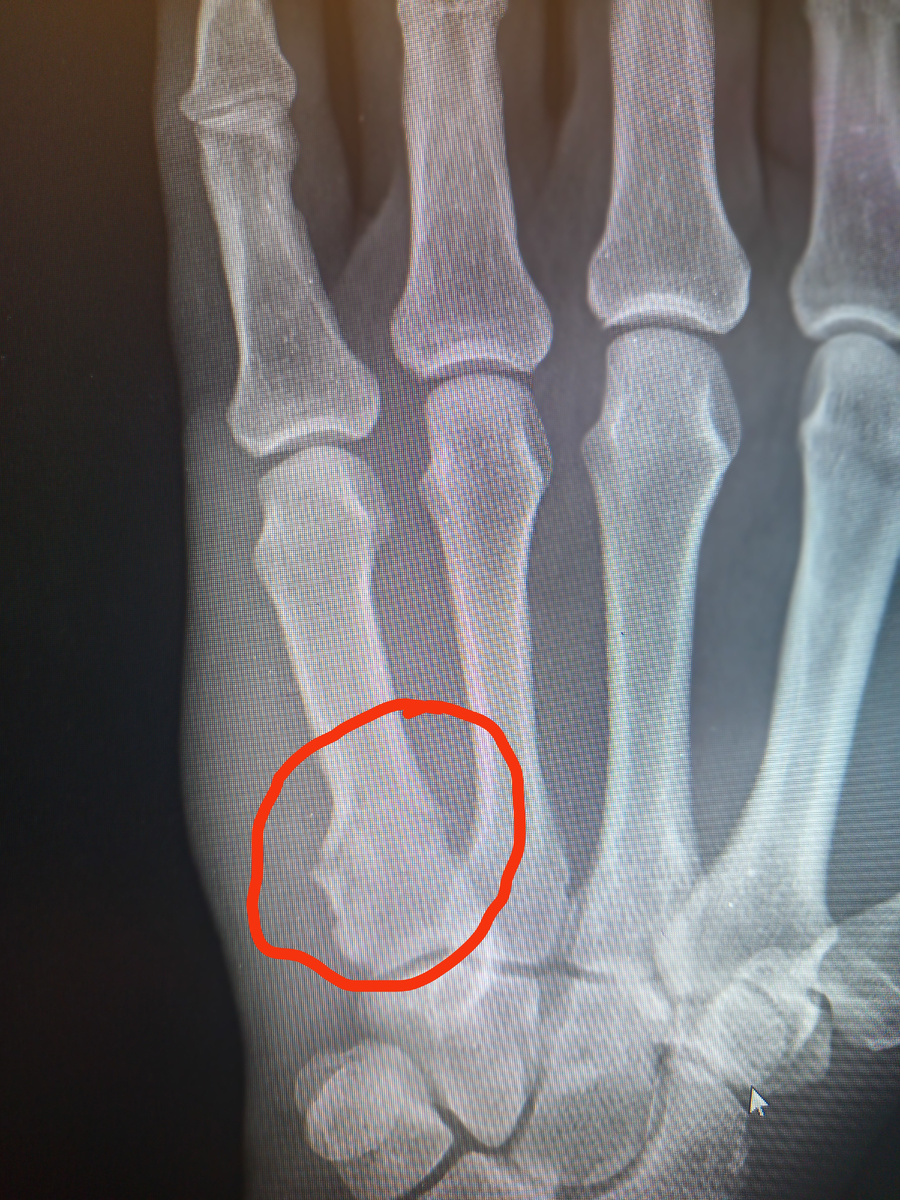

-2

Да , подломил пястную.

Чуть позже в кабинете травматолога, куда я заглянула за уточнением написанного в направлении.

–У вас перелом пятой пястной кости, –говорит врач чудно́му пациенту. –Нужно гипсовать, вы согласны?

–Ой, не знаю, –говорит, –мне надо посоветоваться , можно я маме позвоню, она моя путеводная звезда!

Ага , и еж и госпожа!

–Звоните, только быстро, –разрешает врач.

Судя по разговору , мать пациента сказала ему ,что нужно гипсовать.

–Ой , нет, я так не могу, мне нужно настроиться! –нервничает пациент.

В общем , подписал отказ и ушел. Мужчине 49 лет, если что.